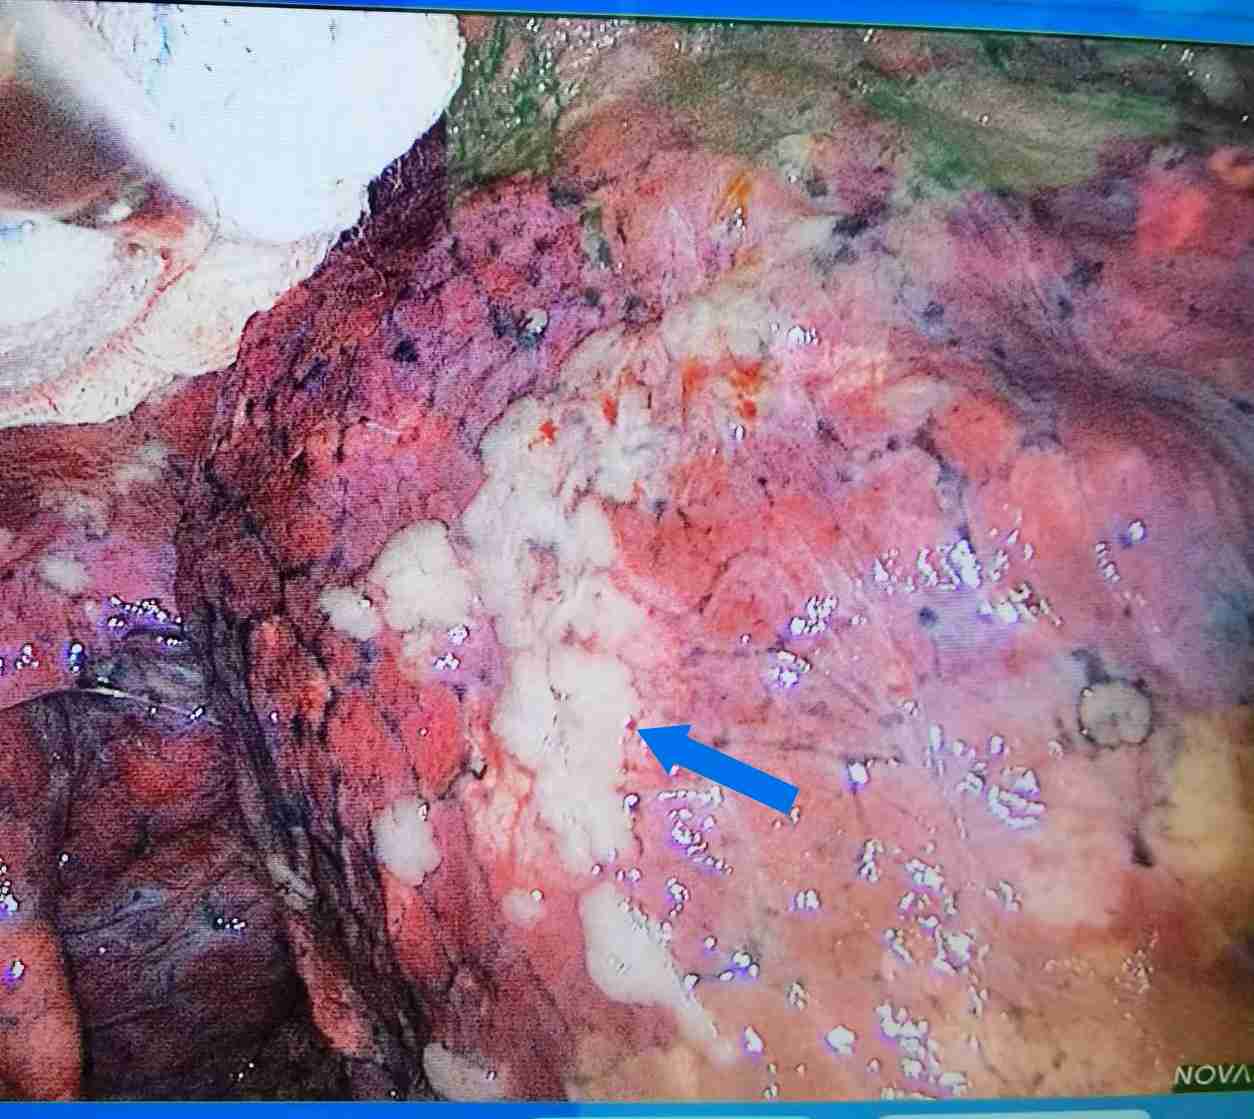

靠近胸膜的结节为何风险高?答案是一旦肿瘤突破胸膜,极容易胸膜腔播散转移,本例为2厘米结节,突破肺表面的胸膜后,出现图1、图2所见的天女散花般转移灶。由1期变为4期,近胸膜的结节相对要积极手,以免肿瘤转移。